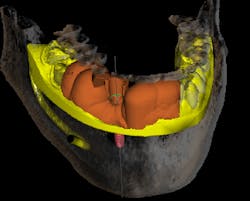

A CBCT scan was taken and imported into the implant planning software. A digital diagnostic wax-up was done by inserting teeth Nos. 26 and 27 into ideal position. With an extremely thin ridge and lack of crestal height, it was determined that space was available for a single implant. Placement was planned for a screw-retained prosthesis with an anterior cantilever (figures 3 and 4).